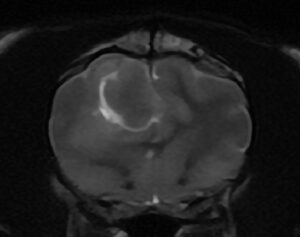

10歳、去勢雄の猫ちゃんで、 1年前からてんかん発作が続いているとのことでした。発作は抗てんかん薬などの内科治療ではコントロールできず、週3~4回発現しているとのことでした。 原因究明のためMRI検査を実施すると、大きな脳腫瘍が認められました。 画像の特徴から髄膜腫が疑われました。

ご家族と相談の結果、できる治療をしてあげたいとのことで、開頭による腫瘍摘出術を実施しました 。病理診断は当初の予測通り、猫の脳腫瘍で最多の髄膜腫でした 。